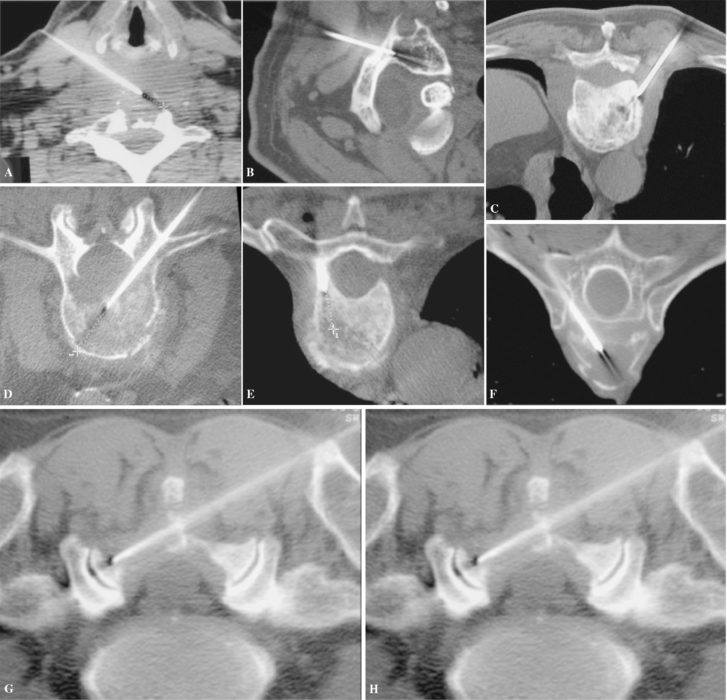

Male patient 47 years old presenting with severe right iliac fossa pain